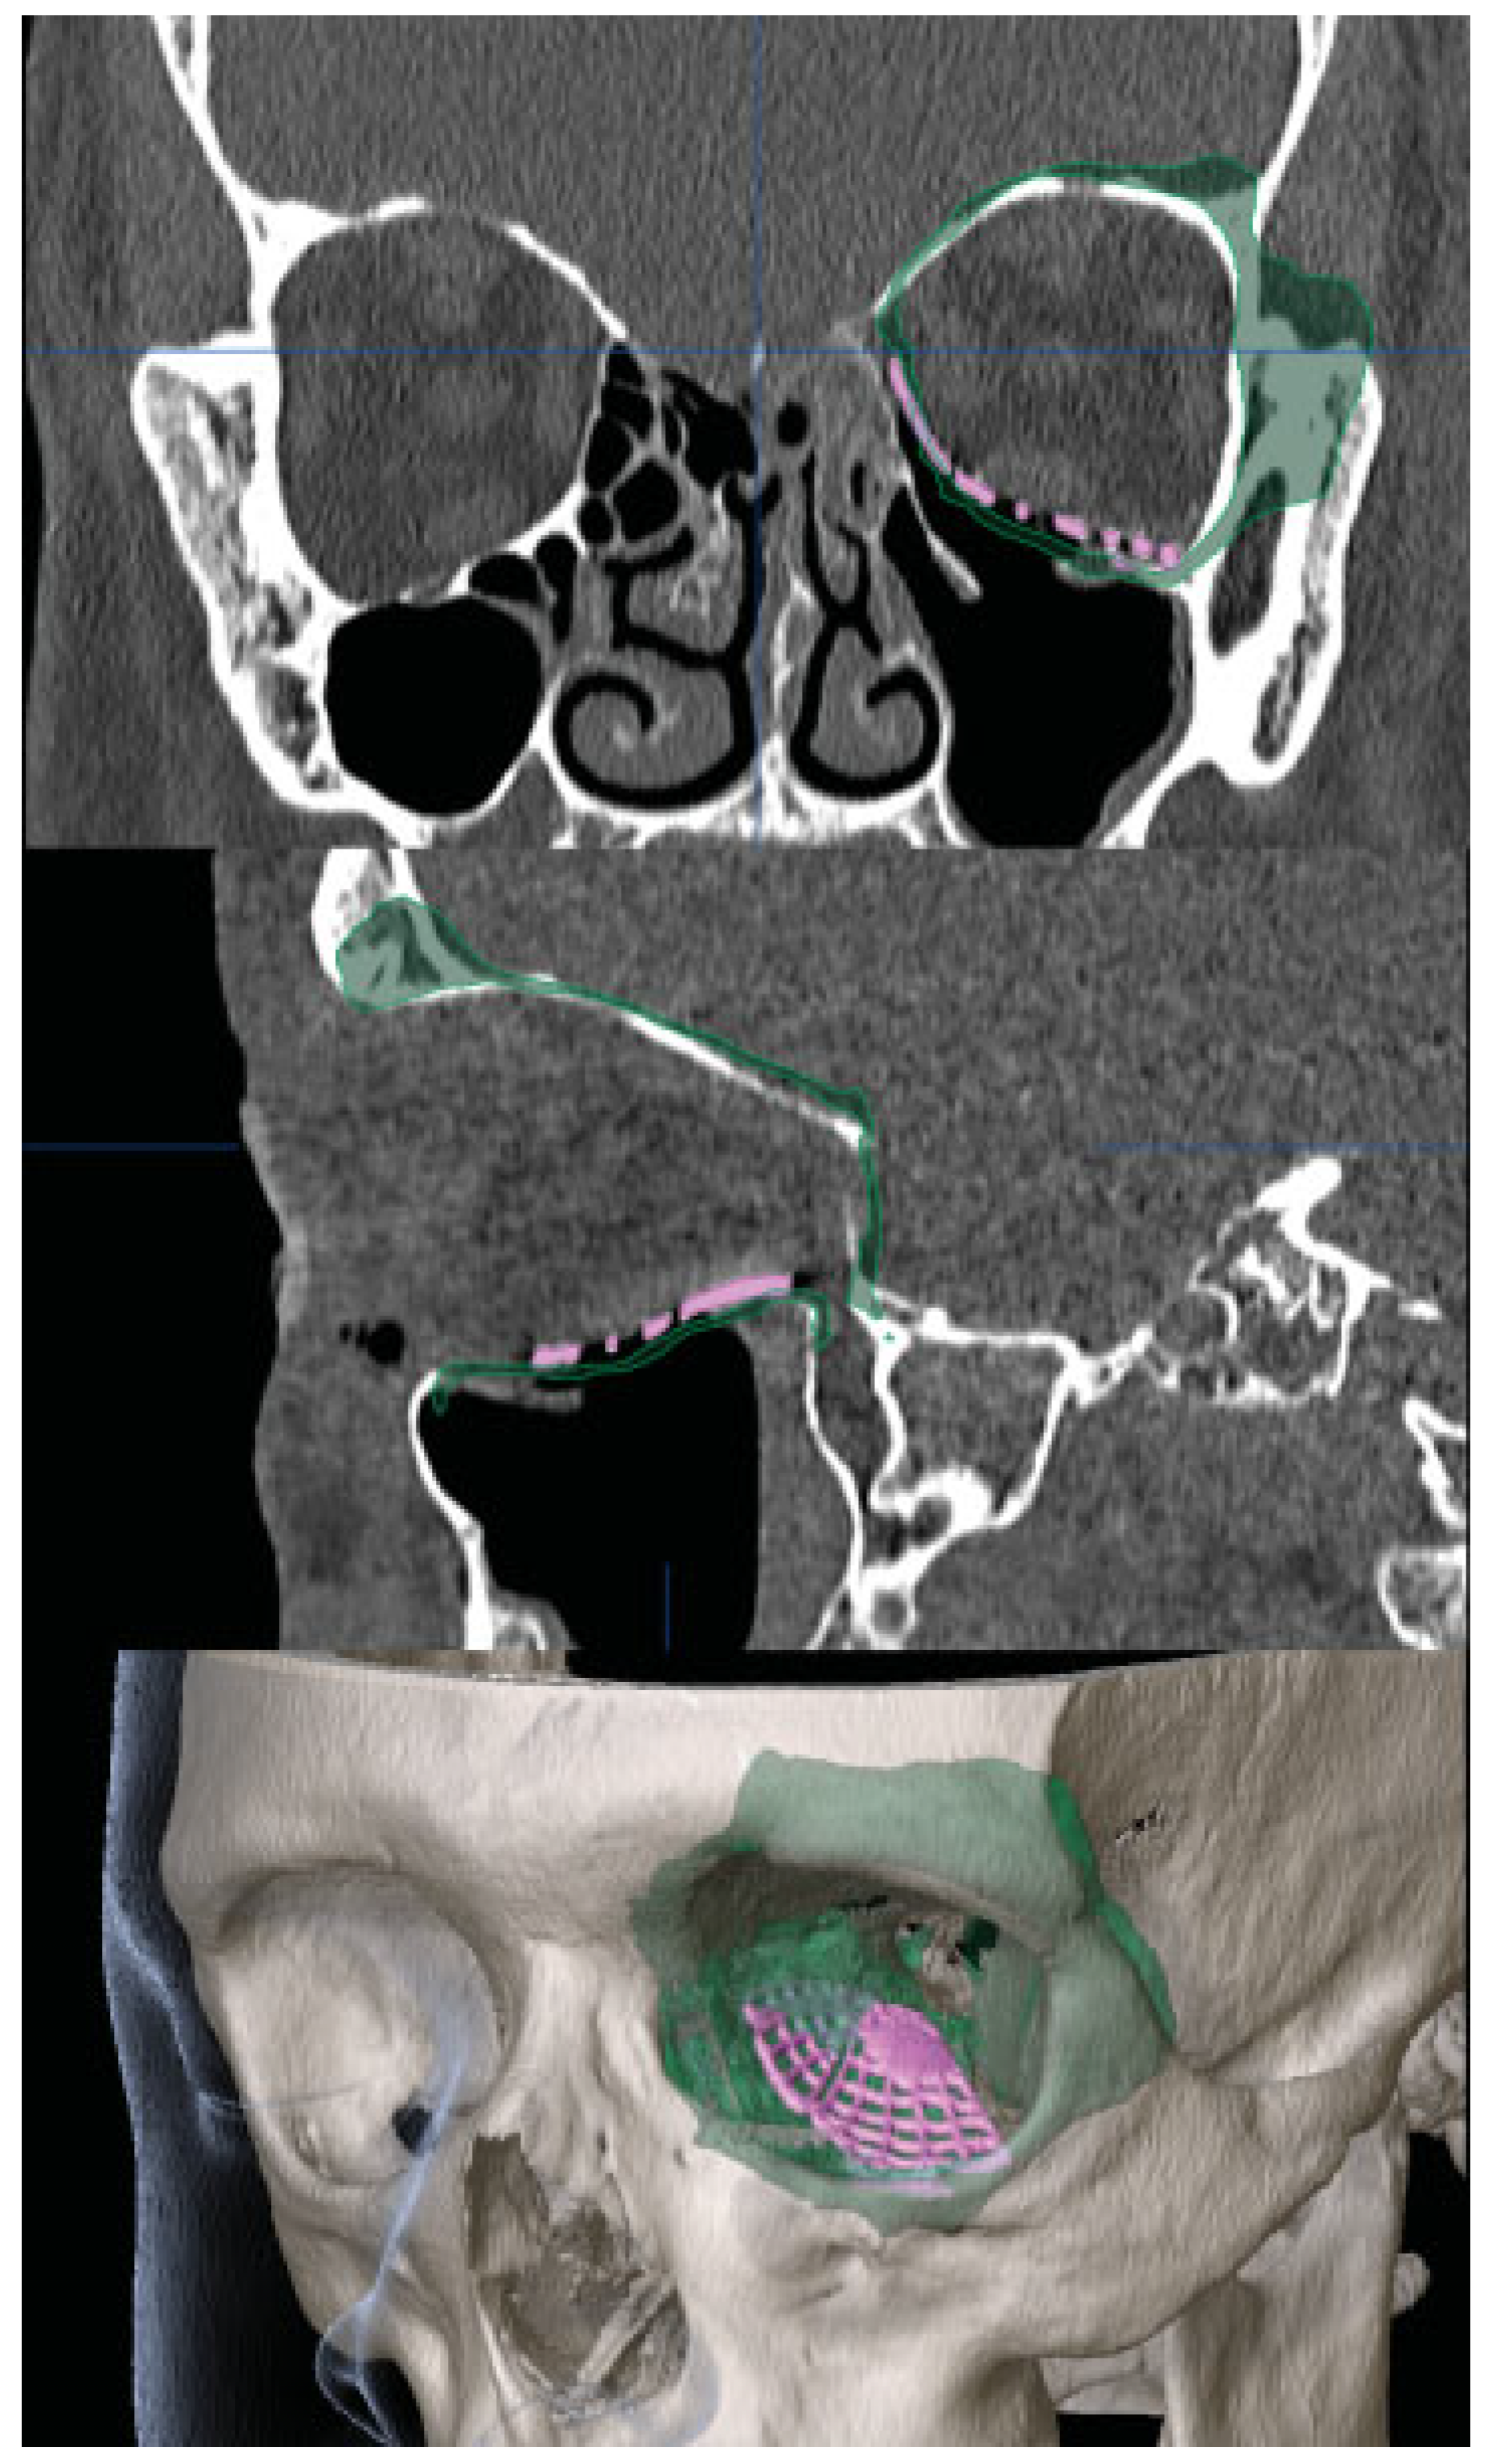

Forced duction testing performed immediately following fracture reduction showed free movement in all directions. Postoperative CT scan showed an appropriately positioned implant and release of the entrapped inferior rectus muscle (Figure 4). At 1-day, 1-week, and 3-month follow-up visits, diplopia and restriction of upgaze had completely resolved (Figure 5).

Figure 4. Postoperative computed tomography demonstrating repair of the orbital floor and medial wall fracture with titanium implant, highlighted in pink. The green overlay represents a mirror image of the right orbital bone segments.